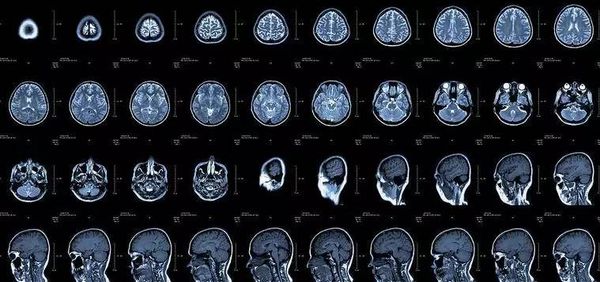

CT

像把面包切片看

CT的检查原理是X线会分层穿过人体,之后通过电脑计算后二次成像,就像把一片面包切成片来看。优点是可以分层看,经计算后可以显示出更多的组织信息。

颈椎腰椎——最佳选核磁,次选CT

颈椎病、腰椎间盘突出等椎间盘疾病需要观察椎间盘与相应的神经根,要想更好观察这些软组织,最优选择就是核磁。同样,对于关节、肌肉、脂肪组织检查,核磁也是首选。